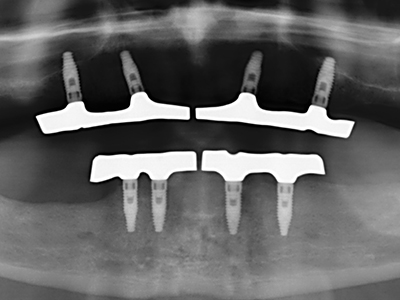

Фиг. 11: Следоперативната панорамна снимка показва вертикалната аугментация и синус лифта.

Фиг. 12: След шест месеца на заздравяване, алвеоларният гребен е добре оразмерен триизмерно.